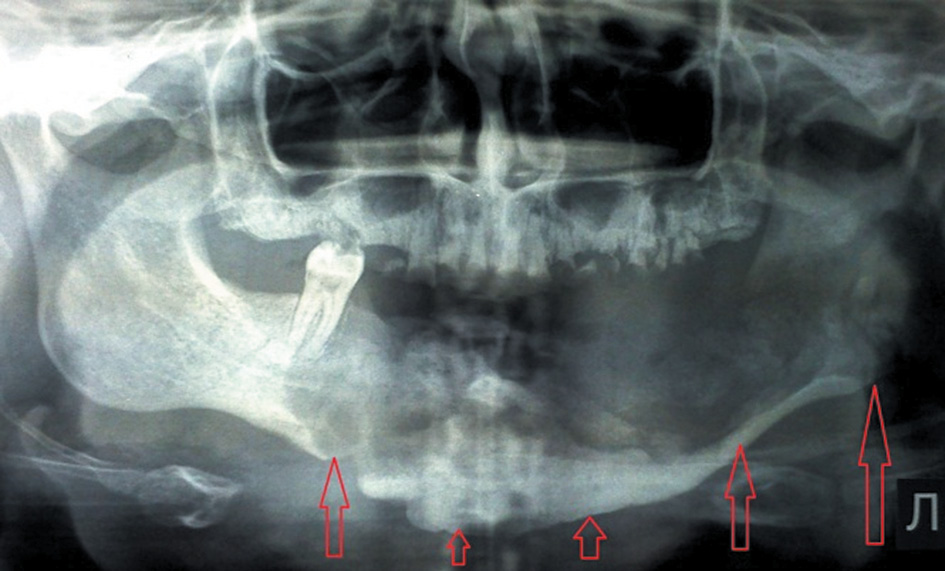

Group 2 (27 patients, including 16 males and 11 females) was characterized by the presence of the signs of sequestration, as a clear demarcation line was found according to OPTG and CBCT of the jaws (Fig. 1).

Fig. 1. Osteonecrosis of the mandible on the left side. The appearance of the demarcation line / Рис. 1. Остеонекроз нижней челюсти слева. Появление демаркационной линии

In addition, the sizes of sequesters varied from an isolated area of the alveolar process within 2–3 teeth to damage in half of the jaw and more. A characteristic was identified in 10 patients with a full-width mandibular lesion. A pronounced thickening and ossification of the surrounding periosteum were found in the form of stratification with the formation of a “bone sheath” surrounding the formed sequestrum, with a width of 5 mm to 1.2 cm (Fig. 2).

Fig. 2. The appearance of the line of ossification of the periosteum in the lesion area along the lower edge of the mandible, creating a “frame” of the newly formed bone / Рис. 2. Возникновение контура оссификации периоста в зоне поражения по нижнему краю нижней челюсти, создающее «каркас» из новообразованной кости